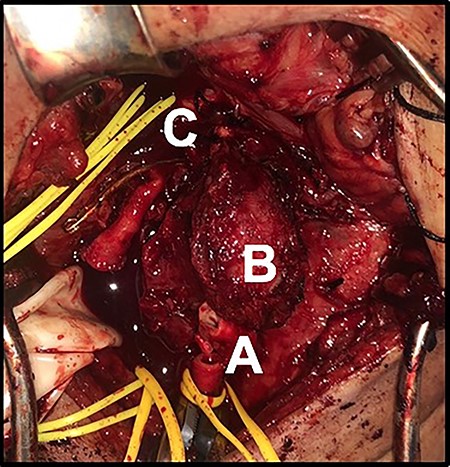

Incision was made from the angle of the mandible towards the chin and subplatysmal flaps were created. The common carotid artery was dissected to obtain proximal control. Distal control was obtained by exposing the internal carotid artery and the ECA cephalad to the tumor (Fig. 3). The tumor was adherent to the posterior wall of the carotid bifurcation, requiring en-bloc resection (Fig. 4) with reconstruction using a common carotid to internal carotid bypass performed with a 6-mm polytetrafluoroethylene (PTFE) interposition graft (Fig. 5). The hypoglossal, vagus and glossopharyngeal nerves were identified, meticulously dissected and preserved. The patient recovered well, had hoarseness of the voice, which resolved after few months with no intervention. The tumor pathology revealed an extra-adrenal paraganglioma positive for chromogranin, synaptophysin and S-100.

(A) Tumor at the bifurcation. Transected common carotid artery. (B) CBTs. (C) Internal carotid artery.